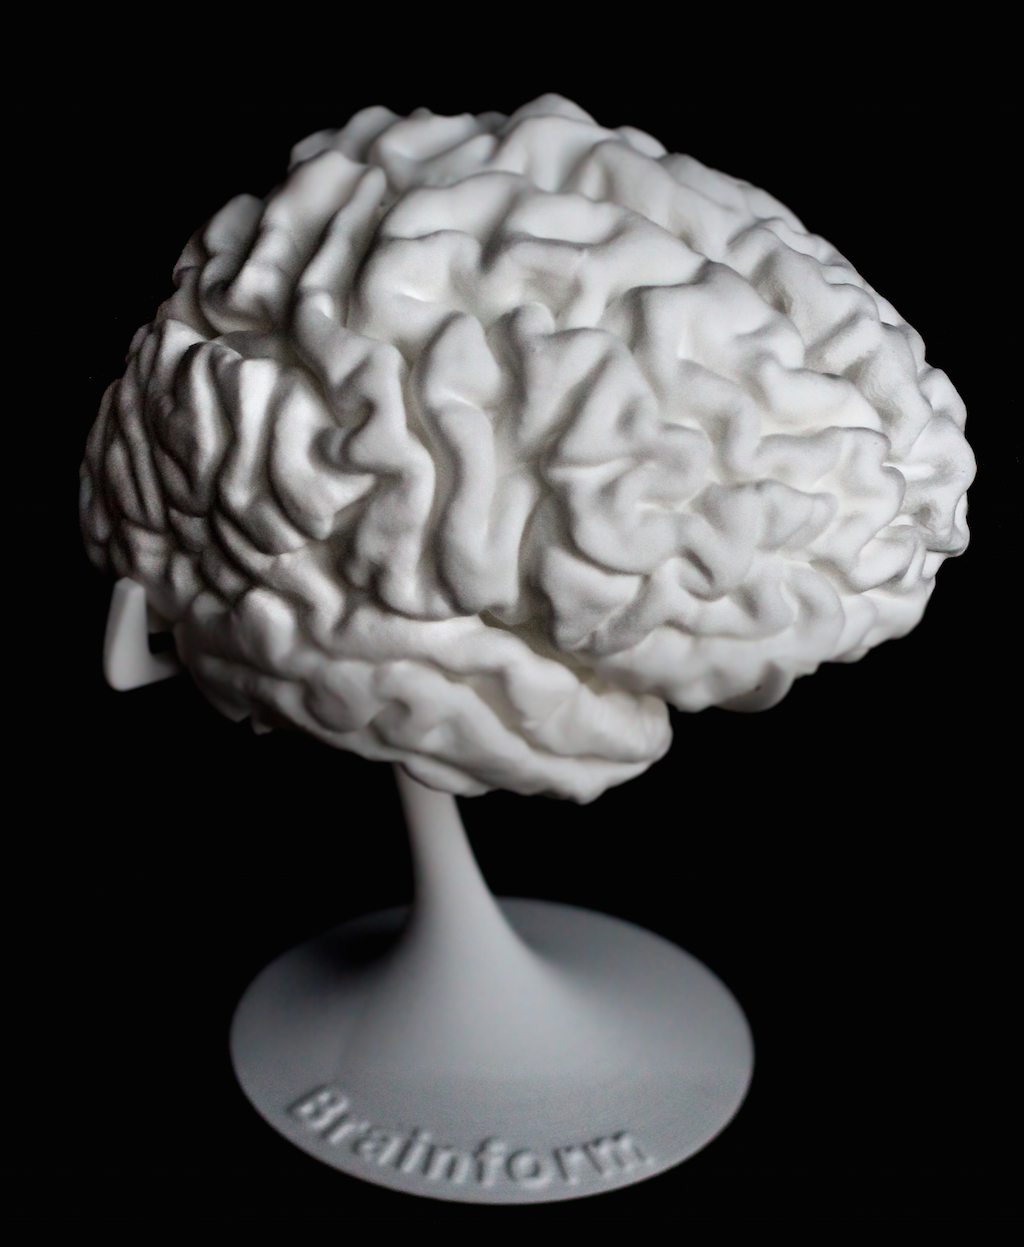

It’s now possible to obtain a 3D printed model of your own brain.

Brainform is a specialized 3D print service that uses MRI scan data to create detailed prints of human brains. While printing a 3D model is pretty straightforward these days, obtaining MRI data might not be.

The prints are literally a “brain on a stem” and appear suitable for educational and personal use. A custom, life-size personal brain print printed on an SLS 3D printer is priced at USD$340, whereas a half-size brain print is priced at USD$110. Stock brain prints are a bit less.

It may seem like a natural progression of technology to see the arrival of a 3D print service that can use MRI scan data to produce a 3D model of your brain, but that’s where we are today. You can actually press a button and receive a print of your brain.